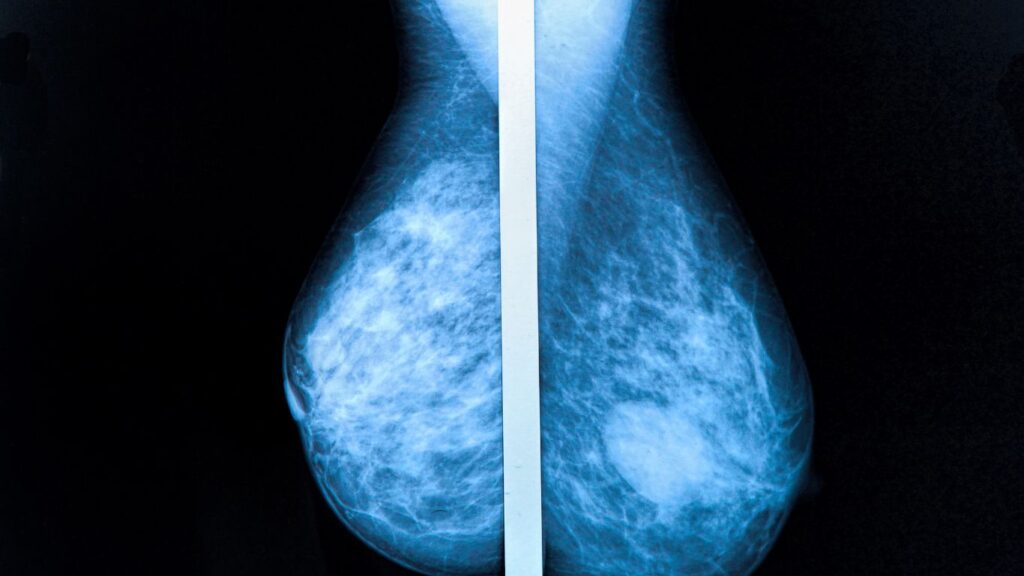

Mamografía: Tu Prevención en Querétaro

En Altaria, entendemos la importancia de la mamografía como una herramienta fundamental en la prevención del cáncer de mama, una de las principales causas de mortalidad entre mujeres en México. Nos comprometemos a ofrecer servicios de mamografía que incorporan tecnología de última generación, asegurando diagnósticos precisos y a tiempo. Este artículo tiene como objetivo concientizar […]

Mastografía Preventiva: Agenda tu Cita en Querétaro

La mastografía preventiva es un estudio fundamental para la detección temprana del cáncer de mama. En Altaria, ofrecemos este servicio en Querétaro utilizando tecnología de vanguardia y un equipo profesional altamente capacitado. Agendar tu cita con nosotros es un paso crucial para cuidar tu salud y detectar cualquier anomalía a tiempo, lo cual contribuye a […]

Cáncer de mama, Mastografía en Querétaro

El cáncer de mama se ha convertido en uno de los problemas de salud más relevantes en nuestro país. En Altaria, reconocemos la necesidad de tomar medidas preventivas efectivas y la mastografía se presenta como una herramienta esencial para la detección temprana del cáncer de mama. Este artículo abordará la importancia de la mastografía no […]